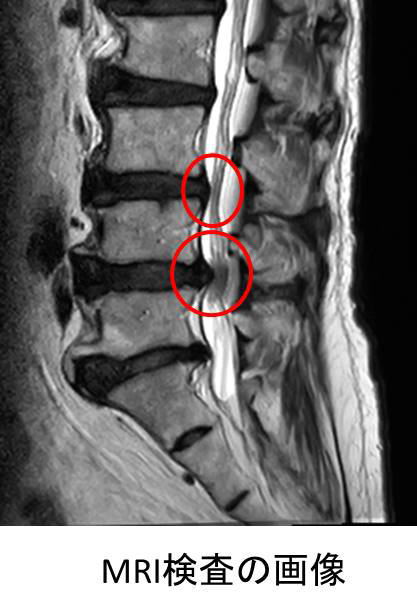

背骨は中央部が空洞で神経の通り道になっており、その空洞を脊柱管といいます。靱帯骨化や加齢による変形などによって腰の骨の脊柱管狭窄が狭くなると、神経が圧迫されて、下肢の痛みやしびれ、運動の障害が出現します。この状態を腰部脊柱管狭窄症といいます。